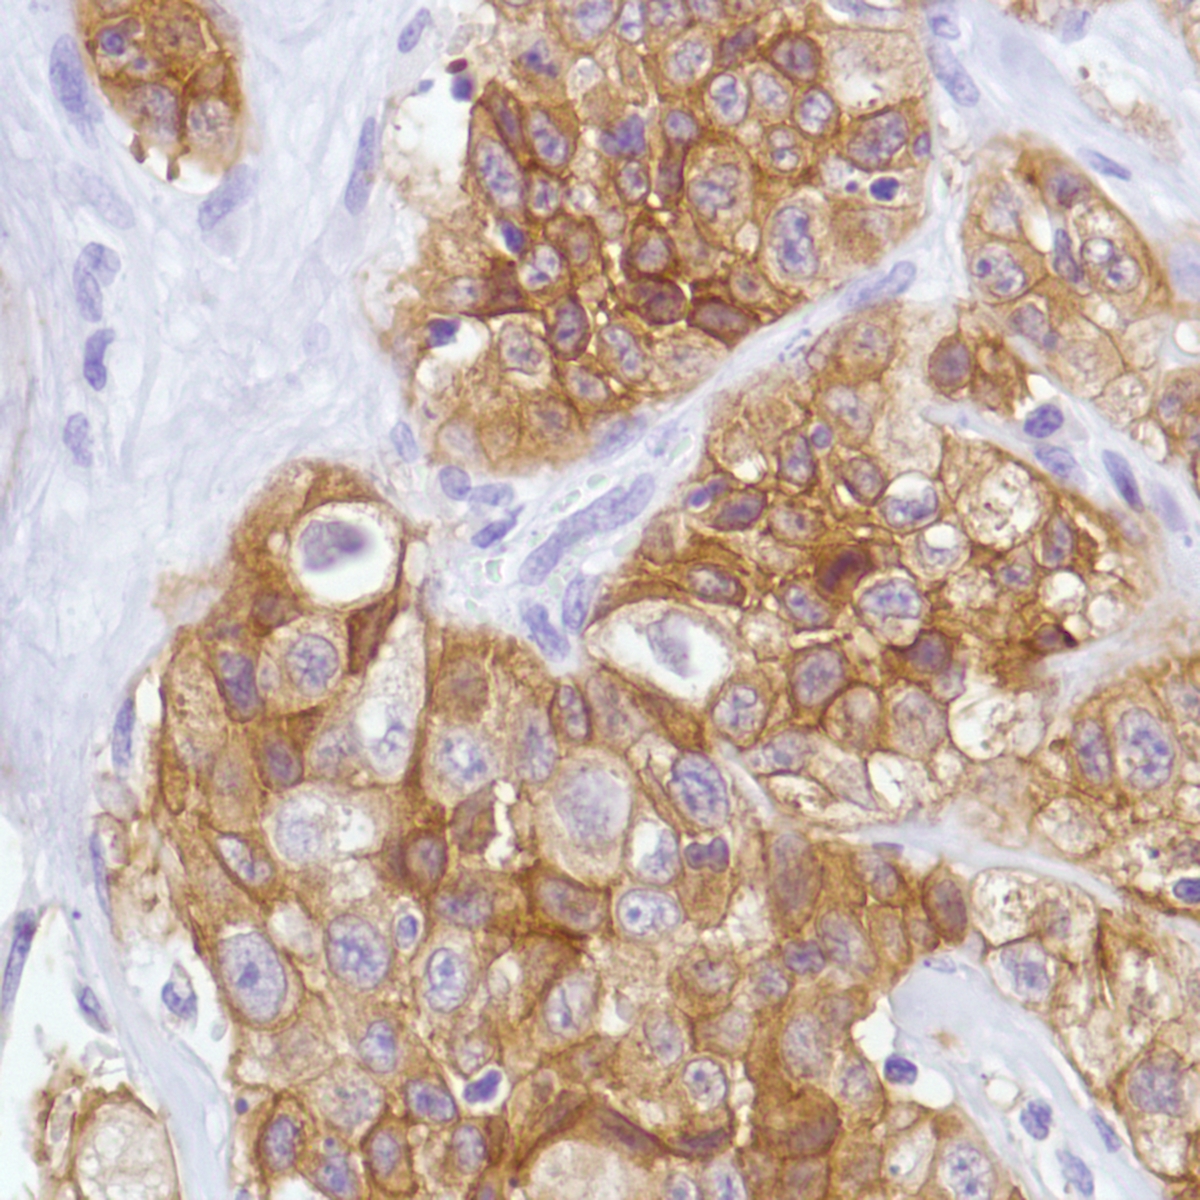

c-Met (SP44)

The c-Met oncogene was originally isolated from a chemical carcinogen-treated human osteogenic sarcoma cell line by transfection analysis in NIH/3T3 cells. The Met proto-oncogene product was identified as a trans-membrane receptor-like protein with tyrosine kinase activity that is expressed in many tissues. The c-Met gene product has been identified as the cell surface receptor for hepatocyte growth factor, a plasminogen-like protein thought to be a humoral mediator of liver regeneration